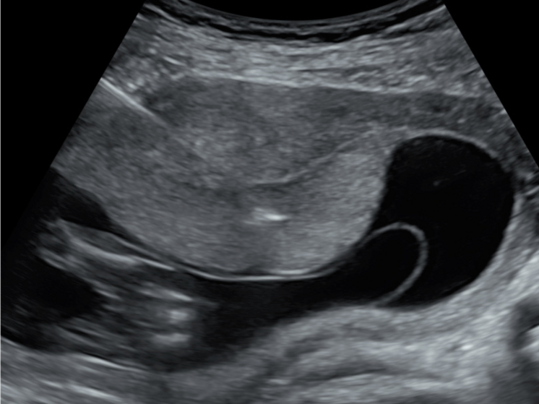

Darstellung der Nackentransparenz bei einem Fetus in 13. SSW

Unter der Nackentransparenz versteht man die mittels Ultraschalls darstellbare Flüssigkeitsansammlung unter der kindlichen Haut im Nackenbereich. Die Dicke dieser Nackenfalte wird zwischen der SSW 11+0 und SSW 13+6 gemessen. Ist diese vergrößert, so ist das Risiko für eine Chromosomenstörung wie zum Beispiel Trisomie 21 (Down-Syndrom) oder bestimmte Fehlbildungen wie etwa Herzfehler erhöht.

Anhand der gemessenen Werte lässt sich mittels einer speziellen Software das individuelle Risiko für die Patientin errechnen. Durch diese Methode können wir in der Pränataldiagnostik und Schwangerenambulanz unter Berücksichtigung des mütterlichen Alters circa 80 Prozent der Kinder mit den schwerwiegendsten Chromosomenstörungen erkennen.

Die Sensitivität kann durch die Kombination mit einer Blutentnahme bei der Mutter zur Bestimmung der Hormone PAPP-A und des freien ß-HCG erhöht werden. Die Entdeckungsrate liegt dann bei circa 90 Prozent. Die Erkennungsrate kann nochmals erhöht werden, indem man im Ultraschall das Nasenbein des Fetus und andere Zusatzparameter (z.B. Ductus venosus) ausmisst.

Das umfangreiche Erst-Trimester-Screening hilft der Patientin bei der Entscheidung für oder gegen eine invasive Diagnostik. Gerade Patientinnen über 35 Jahren, die ein erhöhtes Risiko für eine Trisomie 21 haben, kann so unter Umständen eine invasive Diagnostik erspart bleiben. Das Erst-Trimester-Screening wird in unserer Pränataldiagnostik und Schwangerenambulanz von speziell geschulten, zertifizierten Untersucherinnen und Untersuchern durchgeführt. Im Rahmen der Ultraschalluntersuchung wird der Fetus auch erstmalig auf Fehlbildungen untersucht. Eine ausführliche Feindiagnostik zwischen der 20. und 22. SSW kann diese frühe Ultraschalluntersuchung jedoch nicht ersetzen. In unklaren Fällen oder auf Wunsch der Patienten kann auch eine ergänzende Untersuchung zeIlfreier DNA aus dem mütterlichen Blut ein höheres Maß an Sicherheit erreichen. Ein stufenweises Vorgehen in Abhängigkeit von der Dicke der Nackenfalte wird hierbei empfohlen. Wir beraten Sie hierzu individuell.